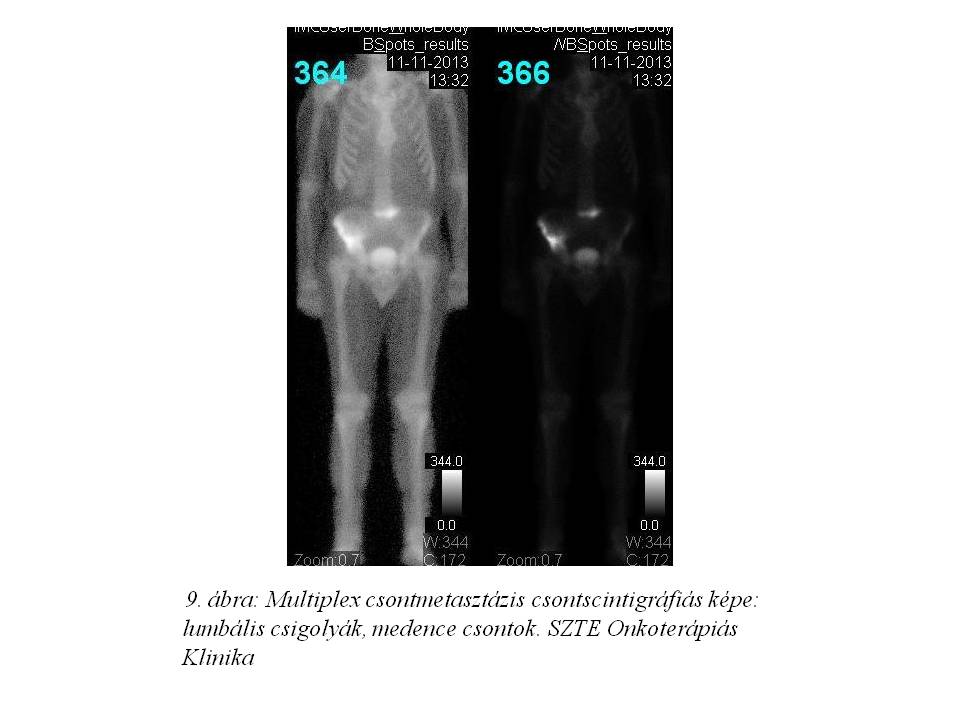

Az 56. ciklus FOLFIRI-bevacizumab immuno-chemotherápiát 2013.09.24-én adtuk, mely utáni CT vizsgálaton (7. ábra, 8. ábra) 80%-os regressziót láttunk az alapvizsgálathoz képest, azonban novum lyticus és scleroticus átépülés jelent meg a jobb csípőlapátban, mely felvetette csontmetasztázis lehetőségét. Ezt egy friss csontscintigráfiás lelet (9. ábra) is megerősítette, és a beteg fokozódó csípő és hátfájdalmai is ezt támasztották alá. Az ossealis propagatio miatt elsővonalas terápiáját felfüggesztettük, fájdalomcsillapítás céljából palliatív irradiatio történt 2013.11.26-tól, a metasztatikusan érintett lumbális IV-V. csigolyákra és medencecsontokra (jobb os ileum, acetabulum), 10x3 Gy frakciódózissal. (10. ábra). Ezen kívül biszfoszfonát (4 mg zoledronsav iv., q4w) kezelés is indult.